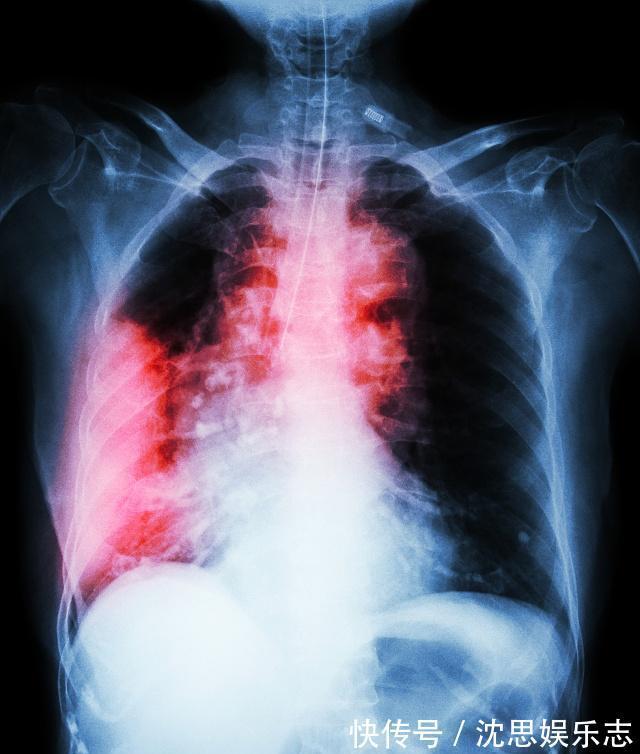

近些年来,社会经济与科技是发展迅速,而人们患上疾病的概率也是越来越高了,像癌症这类的大病也是越来越“放肆”,癌症患病率当然是在逐年上升了,患病人群也是逐渐趋于年轻化,人们都怕癌症!但是仅凭现代的医疗技术,还是不能够完全治愈或者是防止癌症。

87岁的国医大师王绵之,曾在一次访谈中提到过自己患上的两种癌症——肺癌、结肠癌,它当时是很坚强地抵抗过去了!在分享他的抗癌心得的时候,他告诉我们,要记住一句话,并且多吃两种菜,这样就能够起到预防癌症的作用,人才能够更长寿!一句话——开心是最好的抗癌药王绵之和我们大家一样在得知自己患上癌症之后,心情是不好的!快乐是一天,难过也是一天,既然疾病已经发生了,我们为何不调整好自己的心态去面对,王绵之的抗癌方式就是每天都让自己开心点,放空自己的身体,调整呼吸,经常笑嘻嘻……,这样的话会使自己的身体处于一种比较平静的状态中,会少一些压力,身体也会慢慢好起来。